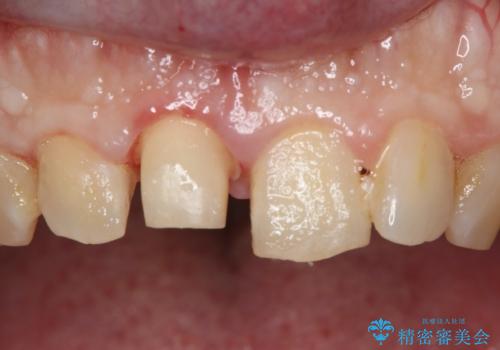

- 上の前歯の一部が欠けてしまったので治療を希望し来院された患者様です。

破折状態から歯髄(歯の神経)は保存できると判断し、クラウンでの治療を計画しました。